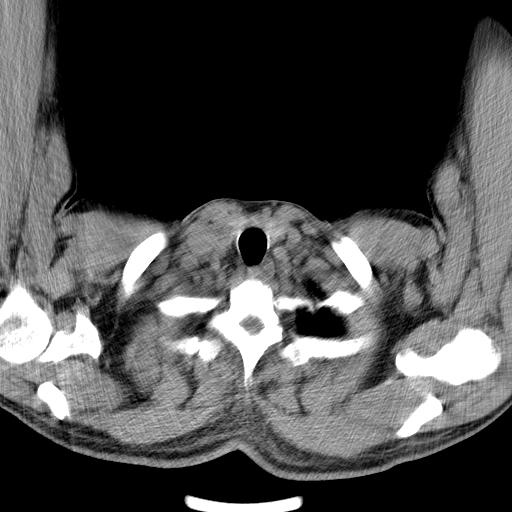

以下是引用zjzjr在2010-3-21 17:39:00的发言:[br]右下中心型肺癌并阻塞性肺炎/不张,纵膈淋巴结肿大,右侧大量胸腔积液,左侧少量胸腔积液

以下是引用zxl51642在2010-3-21 17:06:00的发言:[br]右下中心型肺癌并阻塞性肺炎/不张,纵膈淋巴结肿大,右侧大量胸腔积液,左侧少量胸腔积液,少量腹水。建议纤维支气管镜进一步检查。